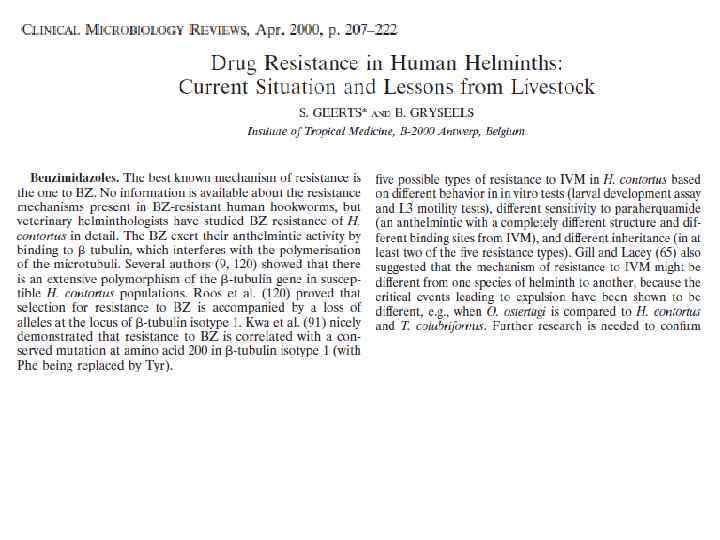

В случае, если тестируются фармакологические противопаразитарные препараты (вермокс, немазол, пирантел, празиквантел, вормин, левамизол), их можно комбинировать с молибденом, реже – с аргинином. Следует помнить также о сочетаниях перечисленных препаратов с травами (порошки, настойки, отвары). Применение прочих препаратов зависит от сопутствующих клинических состояний. © И. Г. Бондаренко, 2011